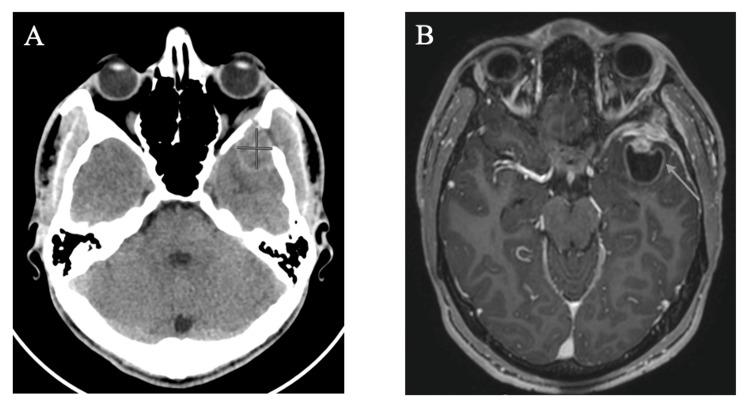

Langerhans cell histiocytosis (LCH) is a proliferative disorder causing normally immune-responsive Langerhans cells to abnormally accumulate in various tissues and organs. Most available data on LCH is derived from pediatric populations, with limited literature focusing on adult LCH, which is rarer. Multisystem involvement in LCH, including central nervous system (CNS) involvement, is often higher risk and poorer prognosis. Standardized treatment recommendations remain limited, particularly in adolescent and young adult (AYA) populations. Discussed below is a case of AYA-onset multisystem LCH with CNS and skeletal system involvement, which was successfully treated with cladribine therapy. An 18-year-old male with no significant past medical history presented with left orbital pain and swelling. Laboratory, imaging, and biopsy results were consistent with a diagnosis of multisystem LCH. The patient was started on cladribine at 0.1 mg/kg/day for 7 days, along with Pneumocystis pneumonia prophylaxis and symptomatic management of facial pain and headaches. After four cycles of cladribine therapy, the patient exhibited symptomatic resolution and complete response of CNS and skeletal lesions. This highlights one potential therapeutic approach yielding a favorable outcome in a borderline case of AYA-onset LCH without targetable mutations on tissue next-generation sequencing (NGS). It also underscores the need for systemic therapy in patients with CNS involvement to avoid future long-term neurodegenerative complications. Further prospective studies and clinical trials are warranted to yield standardized treatment regimens for adult patients with LCH, particularly with multisystem involvement, including CNS.

朗格汉斯细胞组织细胞增多症(LCH)是一种增殖性疾病,可导致正常具有免疫反应性的朗格汉斯细胞在各种组织和器官中异常积聚。关于LCH的现有数据大多来自儿科人群,针对成人LCH的文献有限,而成人LCH更为罕见。LCH的多系统受累,包括中枢神经系统(CNS)受累,往往风险更高且预后更差。标准化治疗建议仍然有限,尤其是在青少年和青年(AYA)人群中。以下讨论的是一例AYA起病的多系统LCH,伴有CNS和骨骼系统受累,该病例通过克拉屈滨治疗成功治愈。一名既往无重大病史的18岁男性出现左眼眶疼痛和肿胀。实验室、影像学和活检结果均符合多系统LCH的诊断。患者开始接受克拉屈滨治疗,剂量为0.1mg/kg/天,持续7天,同时进行肺孢子菌肺炎预防以及面部疼痛和头痛的对症治疗。经过四个周期的克拉屈滨治疗后,患者症状缓解,CNS和骨骼病变完全缓解。这突出了一种潜在的治疗方法,在一例AYA起病的LCH临界病例中取得了良好的治疗效果,该病例在组织下一代测序(NGS)上没有可靶向的突变。这也强调了对于CNS受累患者进行全身治疗以避免未来长期神经退行性并发症的必要性。有必要进行进一步的前瞻性研究和临床试验,以制定针对成人LCH患者,尤其是伴有多系统受累(包括CNS受累)的标准化治疗方案。